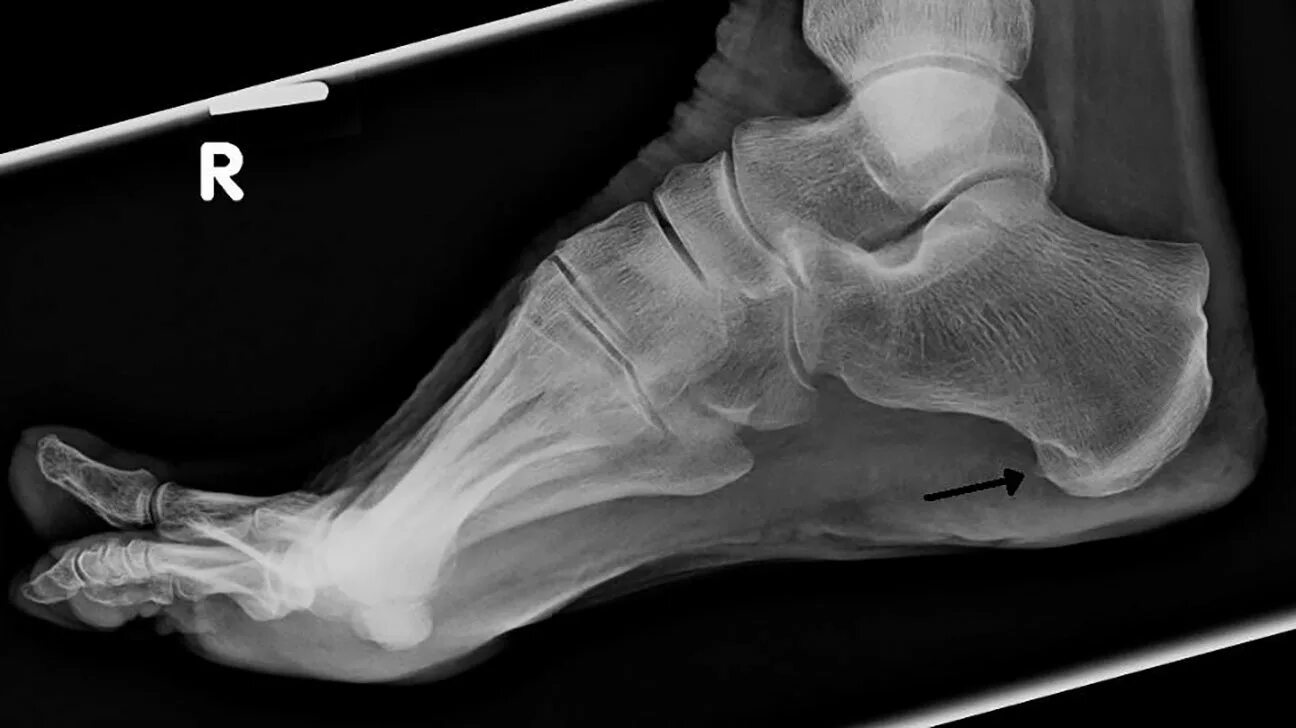

Экзостоз мкб 10